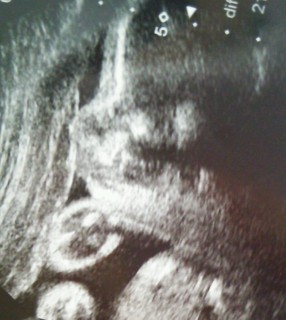

横顔です(^^) 推定体重1518gで、男の子確定のようです(*^^)v

いつも顔の横に手をおいています(^o^)